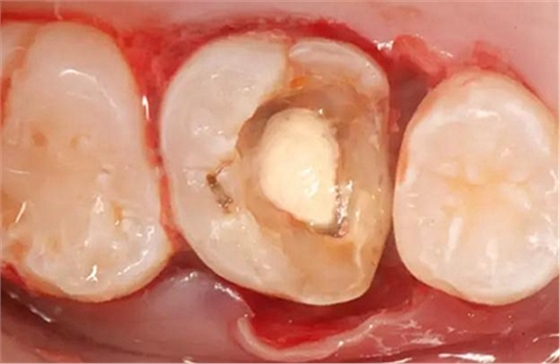

病例一 女性,20歲,大學(xué)生,要求補牙,檢查口內(nèi)可見A6大面積缺損,近中牙齦息肉,拍X片,根管充填物略差,但根周未見明顯陰影,口內(nèi)檢查無叩痛。建議患者冠延長手術(shù)+高嵌體修復(fù)。

患牙遠(yuǎn)中邊緣嵴完整,強度沒有降低,故擬保留遠(yuǎn)中邊緣嵴,高嵌體修復(fù)。首先去除腐質(zhì)及原墊底材料,流體樹脂+3M Z350XT樹脂墊底。局麻下行冠延長手術(shù)。在此需要提及個人的一個觀點。冠延長手術(shù)原則上要求3-6個月以上才能永久修復(fù)。但是個人喜歡后牙肩臺建立在齦上,所以修復(fù)后的修復(fù)體邊緣位于牙齦上方1mm,對牙周的愈合影響較小(如果為齦下邊緣則要慎重),故該患者術(shù)中按照齦上邊緣的設(shè)計進行冠延長手術(shù)。以下為術(shù)中: